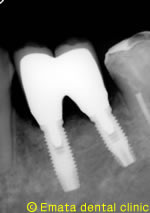

骨誘導再生法をおこない骨の幅を増やす手術(GBR)をしてからインプラント埋入しました。

After

インプラントがはいったお口の状態です。